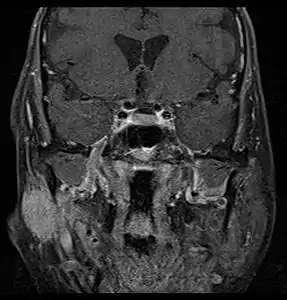

Coronal MRI showing right parotid adenoid cystic carcinoma with perineural spread of tumor: The tumor originates in the right parotid gland and spreads along the trigeminal nerve via the auricuotemporal branch extending intracranially through the foramen ovale at the skull base towards Meckel's cave.

Primary treatment for this cancer, regardless of body site, is surgical removal with clean margins. This surgery can prove challenging in the head and neck region due to this tumor's tendency to show a perineural discontinuous growth, meaning that it follows nerves and different "nests" of the tumor can exist without a connection to the original tumor. Therefore, MRI-images should be analysed following nerve tracts up to the brainstem. Adjuvant or palliative radiotherapy is commonly given following surgery. For advanced major and minor salivary gland tumors that are inoperable, recurrent, or exhibit gross residual disease after surgery, fast neutron therapy is widely regarded as the most effective form of treatment.[13][14][15][16] Chemotherapy is used for metastatic disease. Chemotherapy is considered on a case-by-case basis, as data on the positive effects of chemotherapy are limited. Clinical studies are ongoing, however.